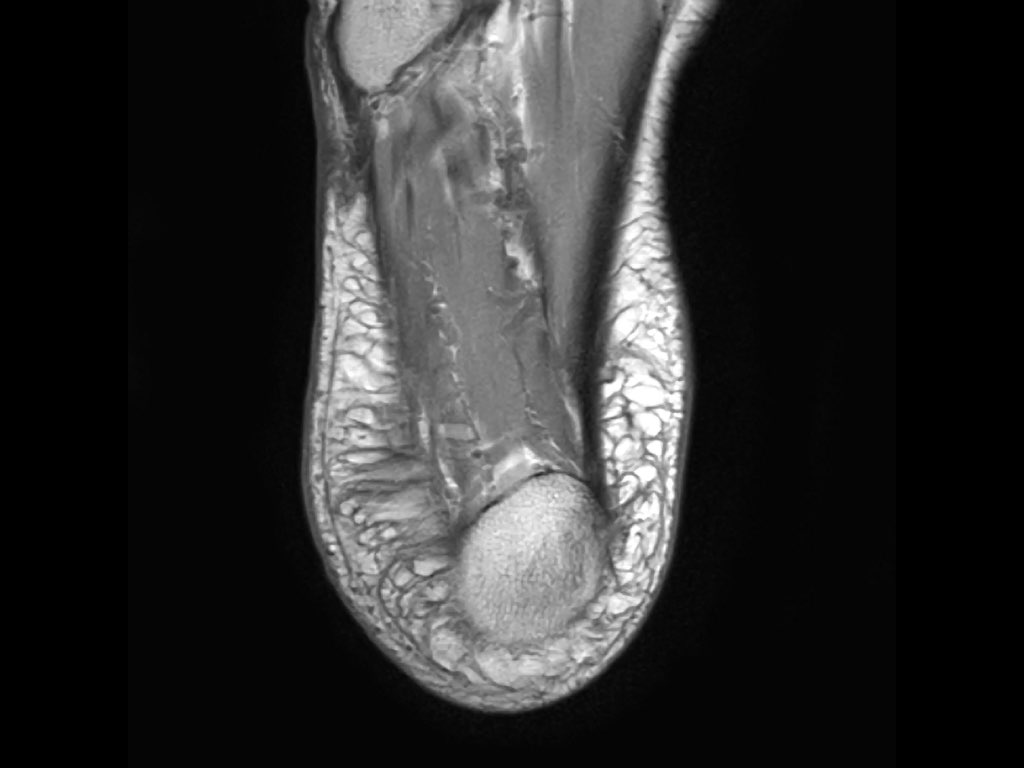

- Khoang ngoài

- Gân cơ mác dài (Peroneus Longus)

- Gân cơ mác ngắn (Peroneus Brevis)